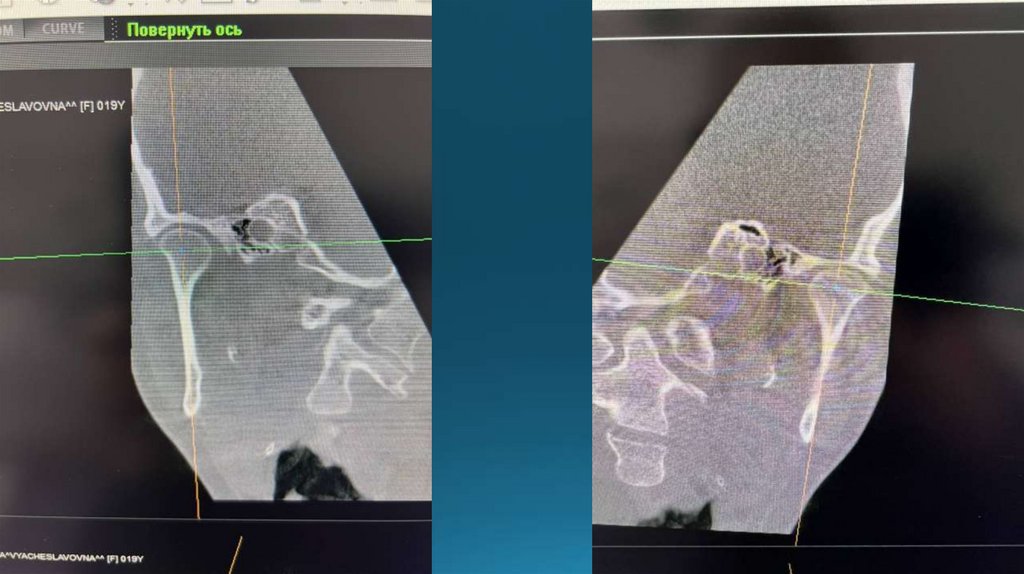

На снимке сужение суставной

щели, начальные признаки

деформирующего

остеоартроза, изменение

формы головки нижней

челюсти